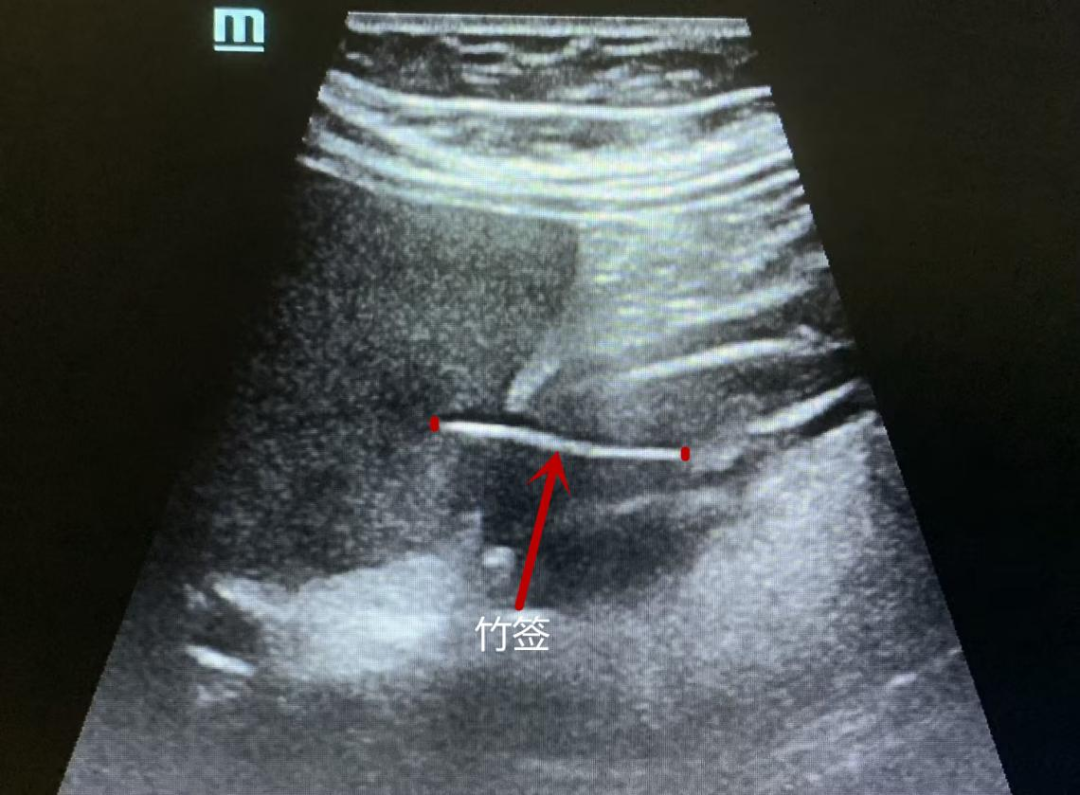

超声科谭庆亭医师反复检测,在患者的胃窦处发现了一个细细长长的异物,经张华斌主任当场会诊后,明确了诊断。此时,患者才努力地回想起,自己发病的前一天曾用竹签吃过包子。超声检查发现这根竹签已经刺破了胃壁,扎入了肝脏。

“胃镜没发现是因为这根竹签的位置很特殊,它穿出了黏膜层,位于黏膜下。”超声科主任张华斌解释说。

而CT和PET/ CT作为临床判别肿瘤的重要手段,主要依靠对组织密度和代谢情况的识别来得出结果,对金属类异物很敏感,但对于竹制品这类与人体软组织密度相似的异物却很难辨别出来。“这根小竹签无论是质地还是位置,对于医学检查来说都十分‘狡猾’。局部增厚的胃壁、肝脏的局灶低回声,以及周围的淋巴结,这些都是异物引起的炎性反应,容易判别为肿瘤倾向。”张华斌解释说。